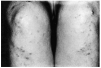

La morfología de las lesiones se ha adaptado de las descripciones previas de la literatura que las divide en lesiones de tipo nodular y de tipo difuso. Las lesiones de tipo nodular se corresponderían en nuestra terminología con lesiones papulosas o papulotuberosas. Este tipo de lesiones fue observado en 28 casos (80%) (fig. 1). Las lesiones de tipo difuso que corresponden a infiltraciones difusas se observaron en cuatro casos (11,4%).

FIG. 1.--Granuloma por erizo de mar. Lesiones del denominado «tipo nodular», con lesiones papulosas y papulotuberosas localizadas en dorso de mano. Nótese la umbilicación central en algunas de las lesiones.

La tendencia al agrupamiento de las lesiones se observó en un 42,8% (15 casos) (fig. 2) y la presencia de tatuaje central en un 20% (7 casos). Un aspecto frecuente fue la presencia de umbilicación central de las lesiones del tipo nodular, identificable en un 68,5%.